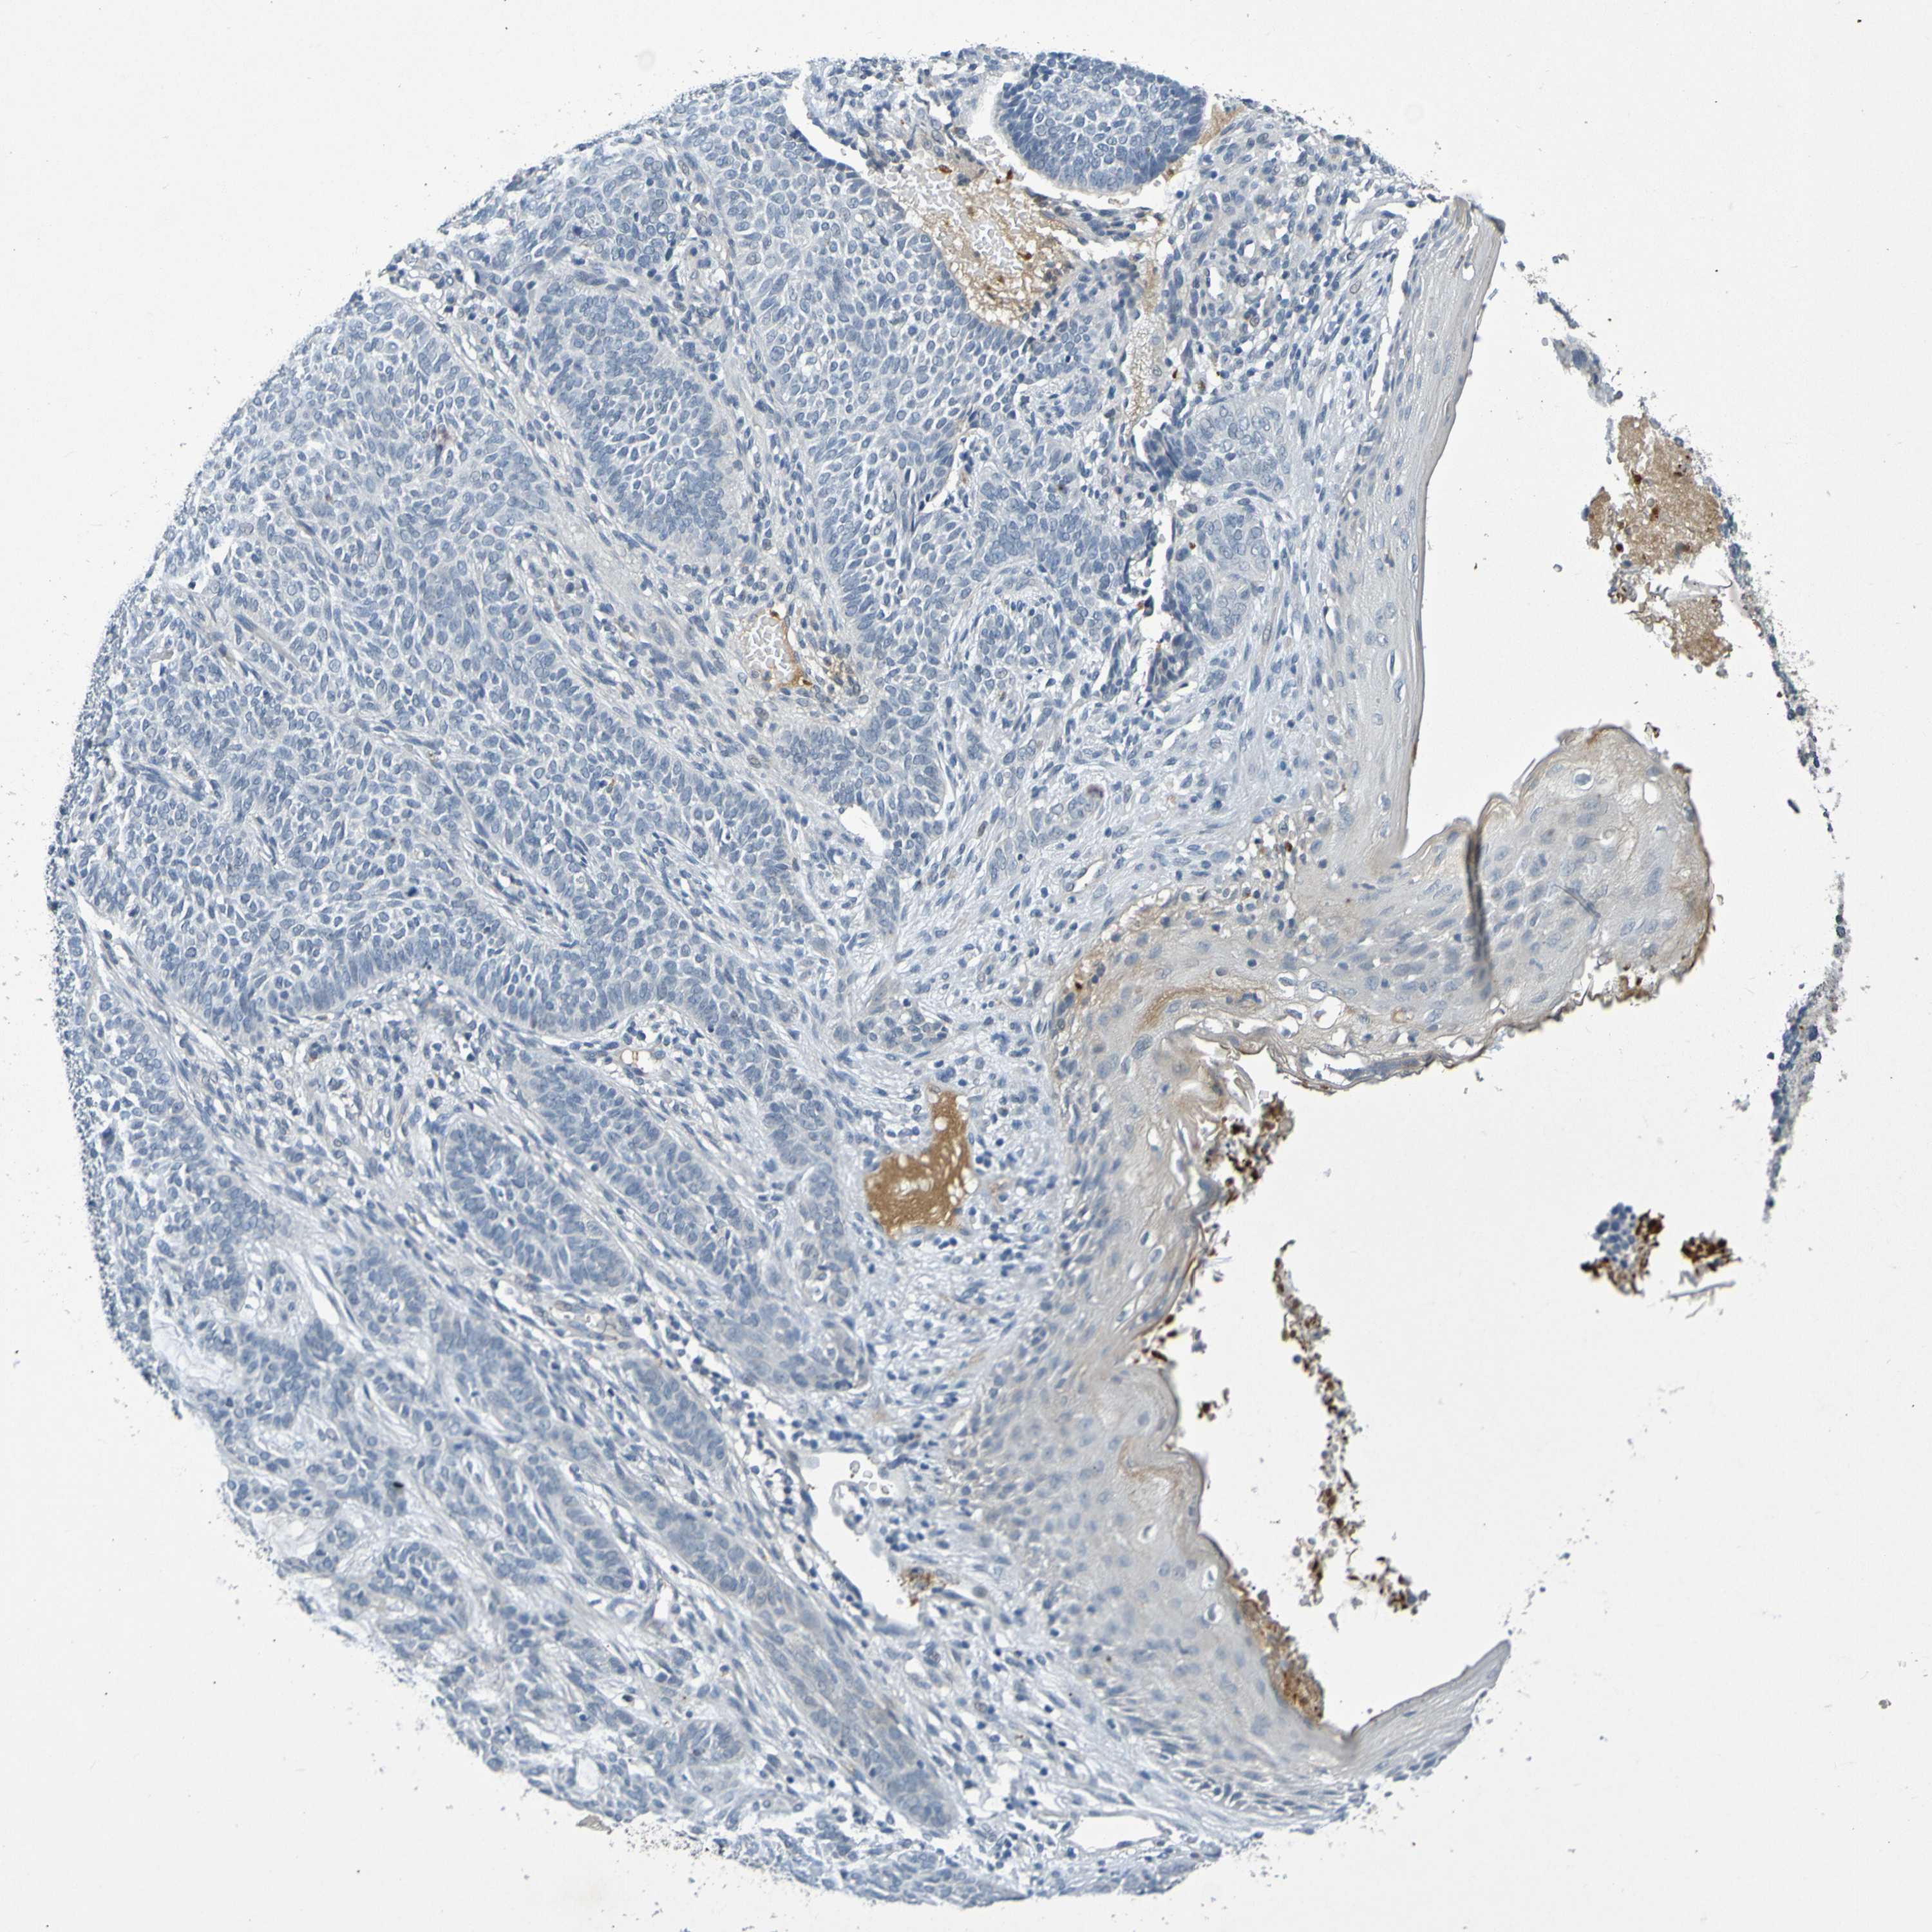

CANCER SKIN CANCER Show tissue menu

Basal cell and squamous cell cancer

SKIN CANCER - Protein expressioni

A mouse-over function shows sample information and annotation data. Click on an image to view it in a full screen mode. Samples can be filtered based on level of antibody staining by selecting one or several of the following categories: high, medium, low and not detected. The assay and annotation is described here.

Each image is clickable and will lead to virtual microscopy that enables deeper exploration of all samples and also displays staining intensity scores, fraction scores and subcellular localization as well as patient and tissue information for each sample.

Antibody HPA071391

Antibody CAB013120

Basal cell carcinoma

Squamous cell carcinoma, NOS